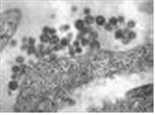

(바이러스) South American hemorrhagic fever virus

Machupo virus

출처:http://phil.cdc.gov/phil/details.asp ID#1869, CDC/Dr. Fred Murphy;Sylvia Whitfield

• 특 성 :Arenaviridae과, Mammarenavirus속, (-)ssRNA 바이러스, 피막 있음